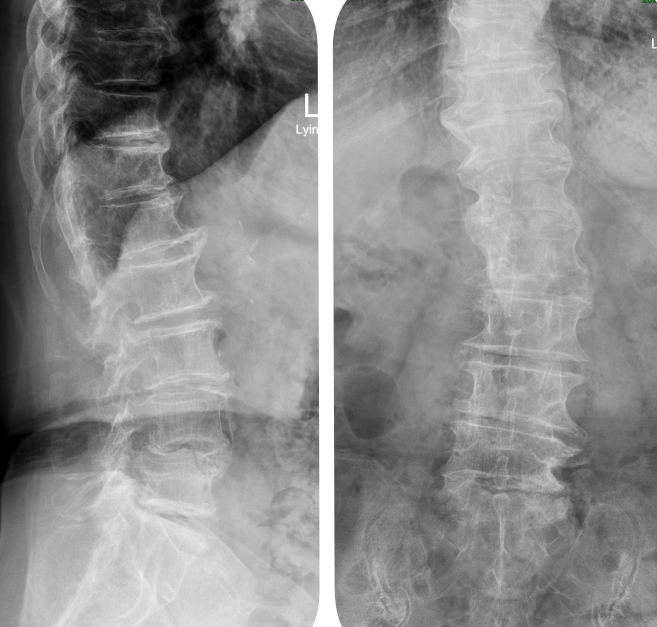

患者术后影像学资料

“我们的手术操作能不能解决目前患者症状?手术中及术后可能遇到哪些困难?会不会引起腰椎不稳或者加重不稳?这个不稳处于腰椎失稳的哪个阶段?”主任姜富祥带领大家就几个核心问题展开病例讨论和研究,最终决定实施导航下腰椎后路滑脱复位椎间盘切除+椎板切除减压+脊髓和神经根松解+植骨融合+椎弓根螺钉内固定术+椎板扩大减压术,最终用骨水泥加强螺钉辅助固定。术中借助导航指引下精准定位,使置钉操作过程又快又准,最终手术的每一个环节都进行得十分顺利。

术后两天刘奶奶便可以下地正常行走,疼痛的症状消失了。“类似这样的手术操作起来具有一定的风险性,需要熟练的脊柱诊疗技术基础及相应设备支撑”,姜富祥主任总结说,如何在存在腰椎滑脱的患者身上,用安全的手术技术完成手术是国内很多大医院和我们病区的努力方向!”